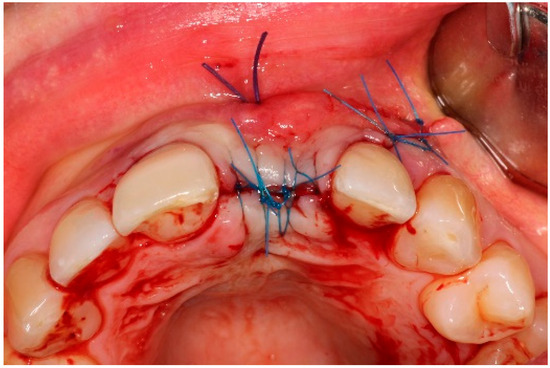

4. Timeline and Diagnostic Assessment

5.2. Non-Surgical Pre-Treatment

5.3. Surgical Treatment